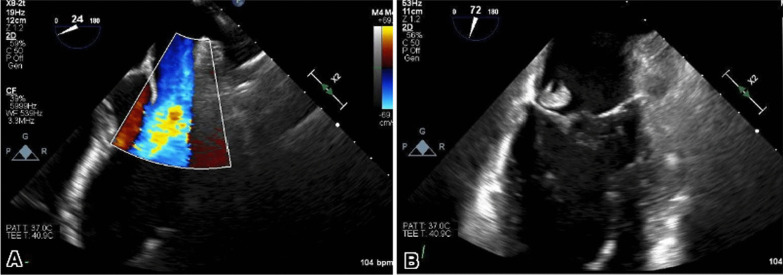

Fig. 2.

(A) Transesophageal echocardiography demonstrating mitral regurgitation depicted by moderate to a severe posterior eccentric jet of mitral regurgitation with evidence of leaflet perforation and color Doppler signal going through the vegetation. (B) Large and rounded echo density measuring up to 1.2 × 1.3 cm attached to the P3 segment of the posterior mitral valve leaflet suggestive of endocarditis, mitral vegetation, and perforation

The patient was treated with heparin, remdesivir, dexamethasone, and baricitinib for one week, but he continued to clinically deteriorate with increased work of breathing, progressive hypoxemia, and high-grade fever, necessitating a transfer to ICU, where he was intubated and received mechanical ventilation. Further investigations were conducted, including a repeat ultrasound of the lower extremities, which showed the thrombus no longer extended to the common femoral vein. His lactate was noted to be elevated, and blood cultures were obtained, which were positive for methicillin-resistant Staphylococcus aureus (MRSA) and the patient was started on IV Vancomycin. The transesophageal echocardiogram (TEE) revealed evidence of native mitral valve endocarditis, characterized by moderate to severe regurgitation and a potential perforation (Fig. 2A, B). Importantly, the TEE did not indicate the presence of a patent foramen ovale.

The patient was transferred to the cardiac ICU and continued on IV Vancomycin. Repeat TEE showed a persistent mobile echo density consistent with vegetation adherent to the atrial aspect of the mitral P3, with an endocarditis-related perforation of the posterior mitral valve and moderate regurgitation. No evidence of perivalvular extension or endocarditis was found on the remaining cardiac valves, and the mitral vegetation appeared slightly smaller than in previous imaging. To assess the electrical activity of the heart, an electrocardiogram (ECG) was performed, yielding normal results without any indications of heart block. The patient was treated with IV Lasix, Losartan, and Metoprolol for acute severe mitral regurgitation, aimed at reducing preload and afterload.